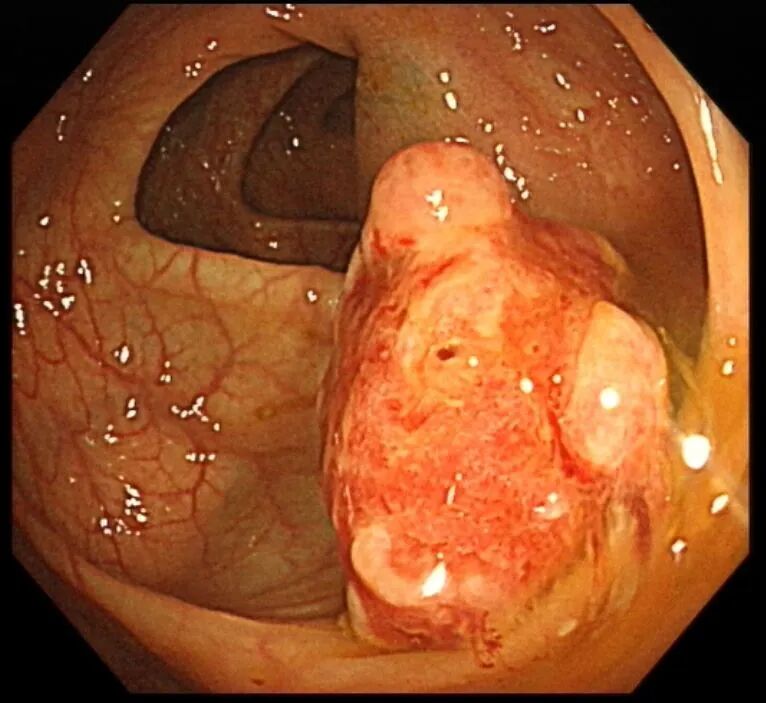

接诊的消化内科医生详细询问了小金的便血特点、发病时长和生活习惯,敏锐意识到这绝非普通痔疮那么简单,当即给他安排了无痛结肠镜检查。负责操作的徐思楠医生在肠镜进镜时,刚进入直肠就看到肠腔内残留的暗红色血迹,循着出血踪迹一路探查,最终在降结肠找到了出血的“元凶”——一枚长径接近3cm的粗长蒂息肉,它的外形就像一颗胖乎乎的蘑菇,蒂部粗壮坚韧,息肉头部表面已经出现了明显的糜烂和渗血,这正是小金反复便血的根源。

考虑到息肉体积大、蒂部粗壮,内部极可能存在粗大的滋养血管,直接切除极易引发术中、术后出血,徐思楠医生当机立断,在和小金妈妈充分沟通、取得书面知情同意后,当场为小金制定了缜密的手术方案,在手术过程中,徐医生先用数枚钛夹精准夹闭息肉的粗蒂根部,彻底阻断息肉的血液供应,再用圈套器完整套住息肉头部,通过规范的电凝电切操作将息肉完整切除,最后再用钛夹严密封闭手术创面,全程几乎无明显出血,操作顺利完成。术后,小金转入住院部,接受了规范的禁食、静脉补液、营养支持等治疗,未出现出血、穿孔等并发症,很快恢复了正常饮食,顺利康复出院。术后病理结果最终揭晓,这枚息肉为幼年性息肉,属于良性病变,后续只需定期复查肠镜即可。